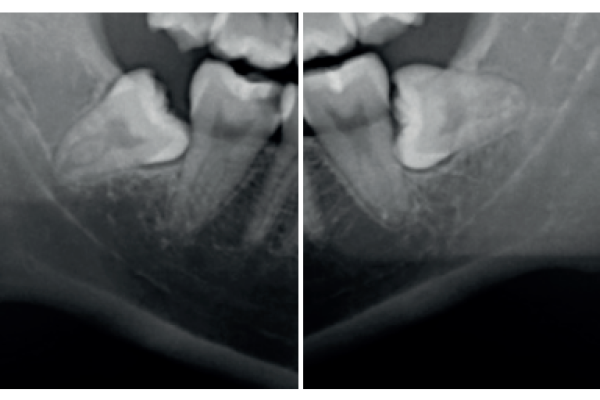

Prevención de defectos periodontales tras la exodoncia de terceros molares inferiores con injerto de dentina autógena: evaluación a 6 meses de un caso clínico